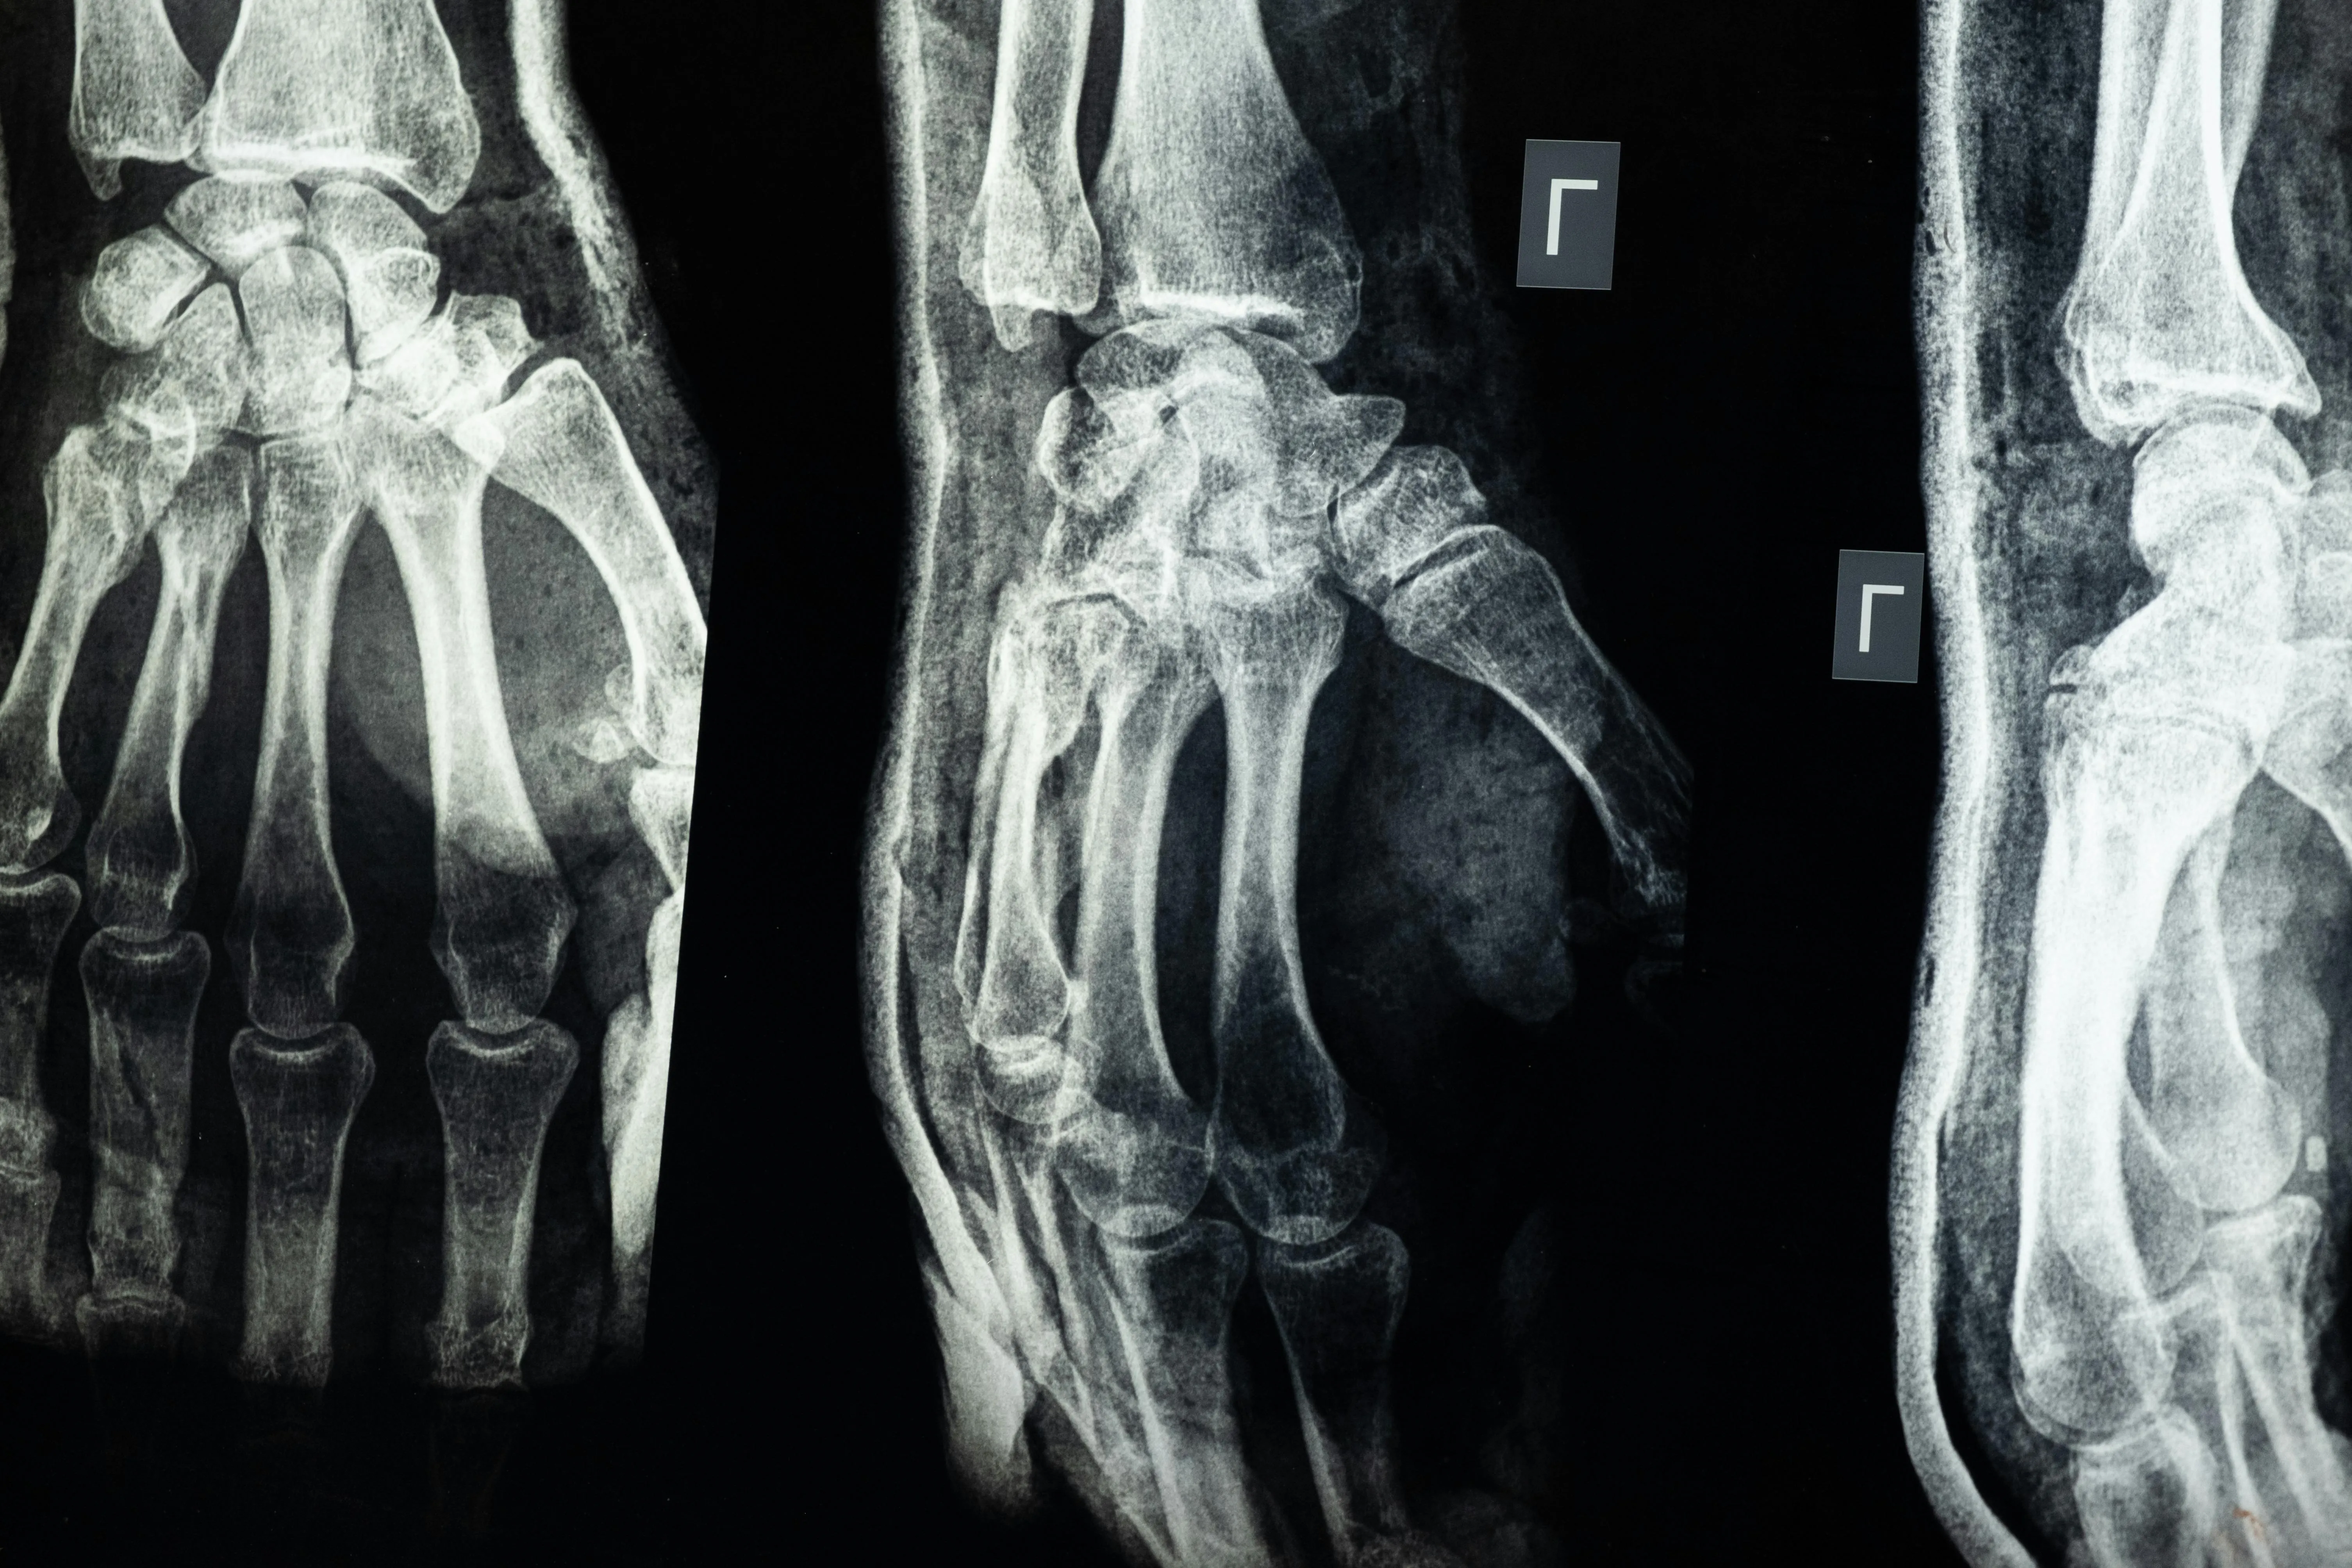

Radiografía detallada mostrando estructura ósea

Radiografía detallada de muñeca mostrando estructura ósea